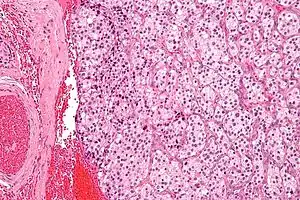

| Micrograph of a carotid body tumor (a type of paraganglioma). | |

The paragangliomas appear grossly as sharply circumscribed polypoid masses and they have a firm to rubbery consistency. They are highly vascular tumors and may have a deep red color.

On microscopic inspection, the tumor cells are readily recognized. Individual tumor cells are polygonal to oval and are arranged in distinctive cell balls, called Zellballen.[8] These cell balls are separated by fibrovascular stroma and surrounded by sustentacular cells.

Micrograph of a carotid body tumor